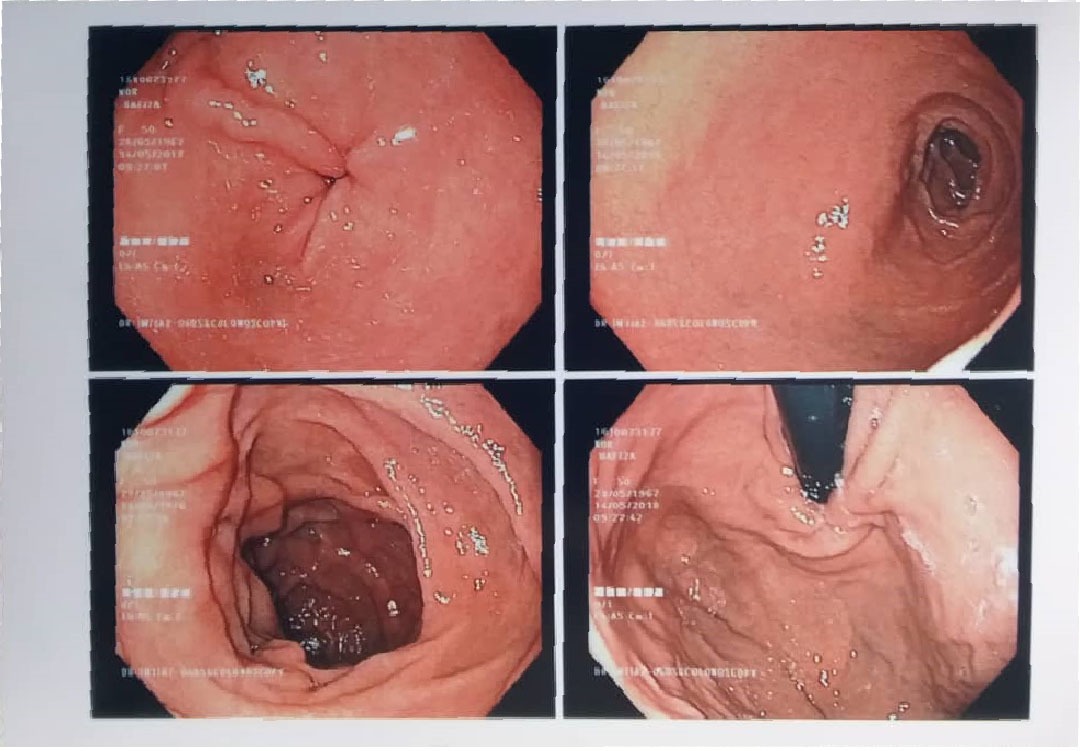

Pada tahun 2016, saya mula mengalami ketidakselesaan yang teruk pada bahagian perut, pergerakan usus yang tidak teratur, dan gejala membimbangkan yang mengganggu kehidupan seharian. Apabila menerima diagnosis serius mengenai kesihatan sistem pencernaan saya, dunia terasa gelap seketika. Saya bimbangkan masa depan suami dan anak-anak. Alhamdulillah, suami saya terjumpa risalah Ibnu Sina Wellness™ di surau dan mencadangkan agar saya mencubanya sebagai jalan sokongan ke arah pemulihan.

Saya memulakan perjalanan bersama Ibnu Sina Wellness™ pada Januari 2017 dengan penuh harapan. Hasilnya sungguh luar biasa! Dalam tempoh beberapa bulan, pemeriksaan menunjukkan sistem dalaman saya beransur-ansur pulih dengan sendirinya. Menjelang 2018, pemerhatian klinikal menunjukkan saluran pencernaan saya telah kembali ke tahap yang sangat sihat dan cergas. Pendekatan ini bukan sahaja menyokong pemulihan fizikal, malah menguatkan kesejahteraan emosi dan spiritual saya.